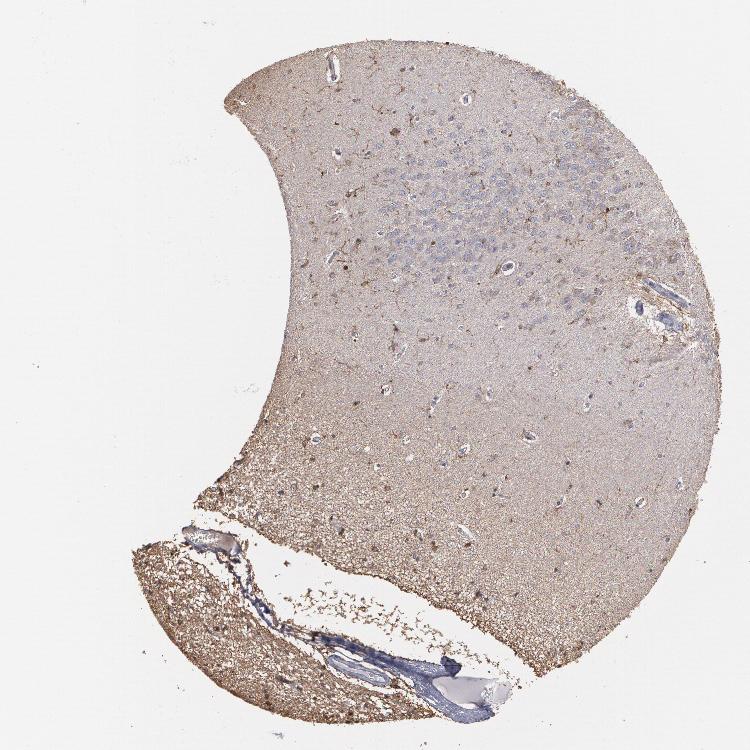

HIPPOCAMPUS - Antibody stainingi

Antibody staining in the annotated cell types in the current human tissue is reported as not detected, low, medium, or high, based on conventional immunohistochemistry profiling in selected tissues. This score is based on the combination of the staining intensity and fraction of stained cells.

Each image is clickable and will lead to virtual microscopy that enables deeper exploration of all samples and also displays staining intensity scores, fraction scores and subcellular localization as well as patient and tissue information for each sample.

Antibody HPA001536Antibody CAB035996

Glial cells MediumNot detected

Neuronal cells MediumNot detected